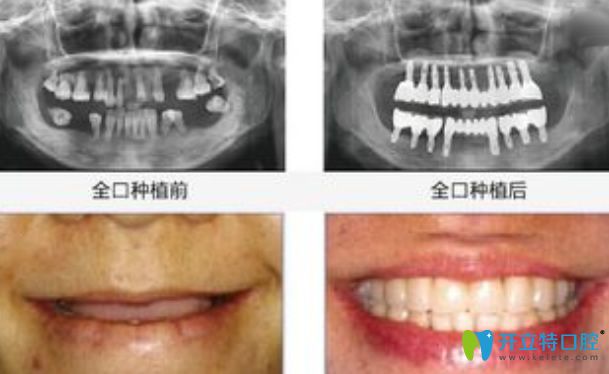

全口種植牙前后對比圖